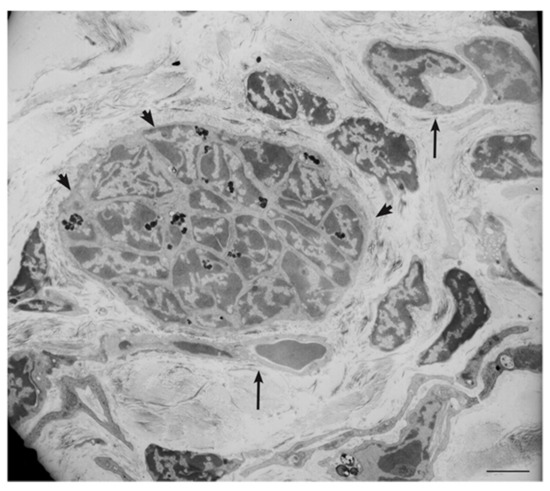

4. Ultrastructural and Immunomorphological Relationships Between the Vascular and Neural Compartments of Head and Neck Paragangliomas

- Verginelli, F.; Perconti, S.; Vespa, S.; Schiavi, F.; Prasad, S.C.; Lanuti, P.; Cama, A.; Tramontana, L.; Esposito, D.L.; Guarnieri, S.; et al. Paragangliomas arise through an autonomous vasculo-angio-neurogenic program inhibited by imatinib. Acta Neuropathol. 2018, 135, 779–798. [Google Scholar] [CrossRef] [PubMed]